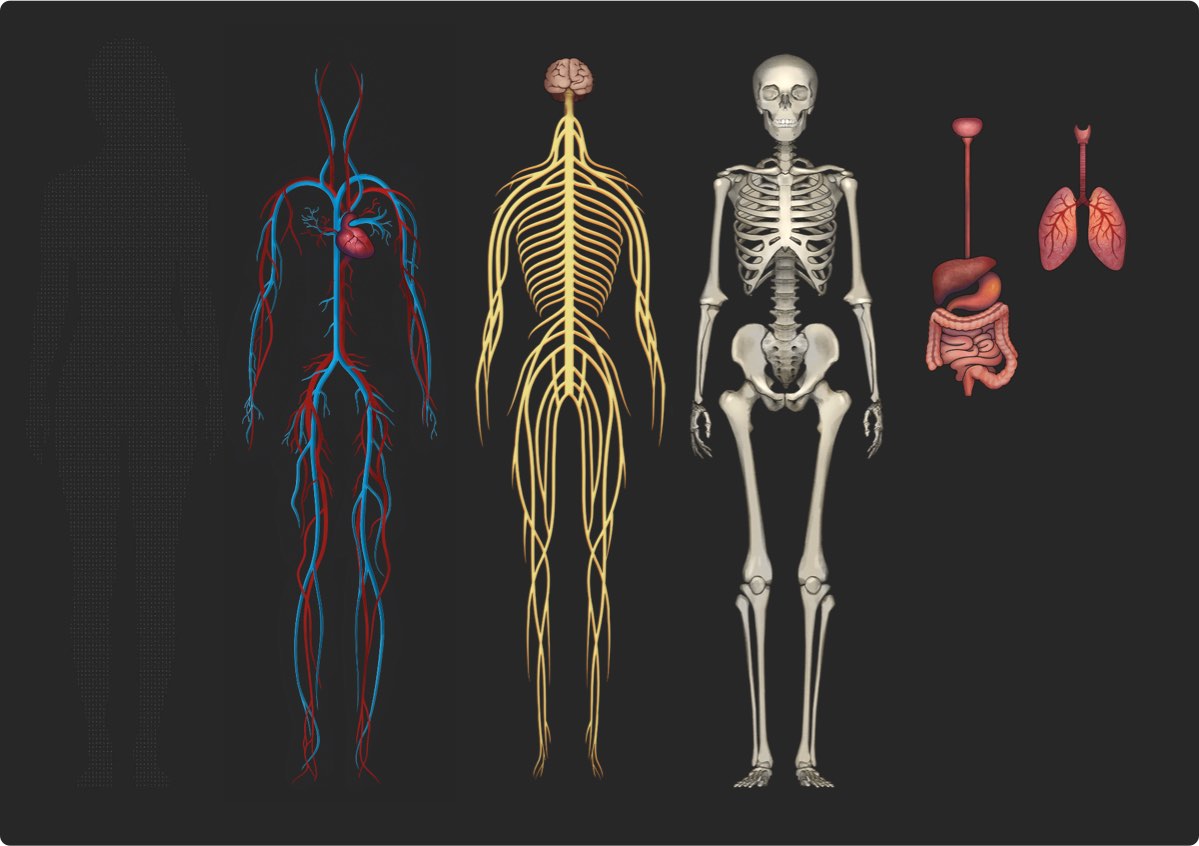

Considering a way to present genetics based on themes.

—an insert about genetic factors influencing that sphere of life;

The introduction is followed by a block about the influence of genetics on each sphere of human life. Drawing "the best illustration of a call on the internet."

Drawing additional icons and technical graphics.